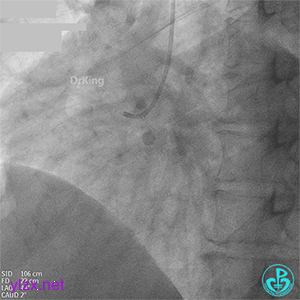

07 2个月后再次造影

处理前降支病变,导丝Pilot 50通过LAD病变到达远段,沿导丝送入穿通导管至远段,回抽有血,造影提示在真腔。

PTCA球囊扩张后无前向血流,以硝普钠反复行冠脉内局部药物释放治疗术。

复查造影提示LAD血流恢复TIMI血流2-级。